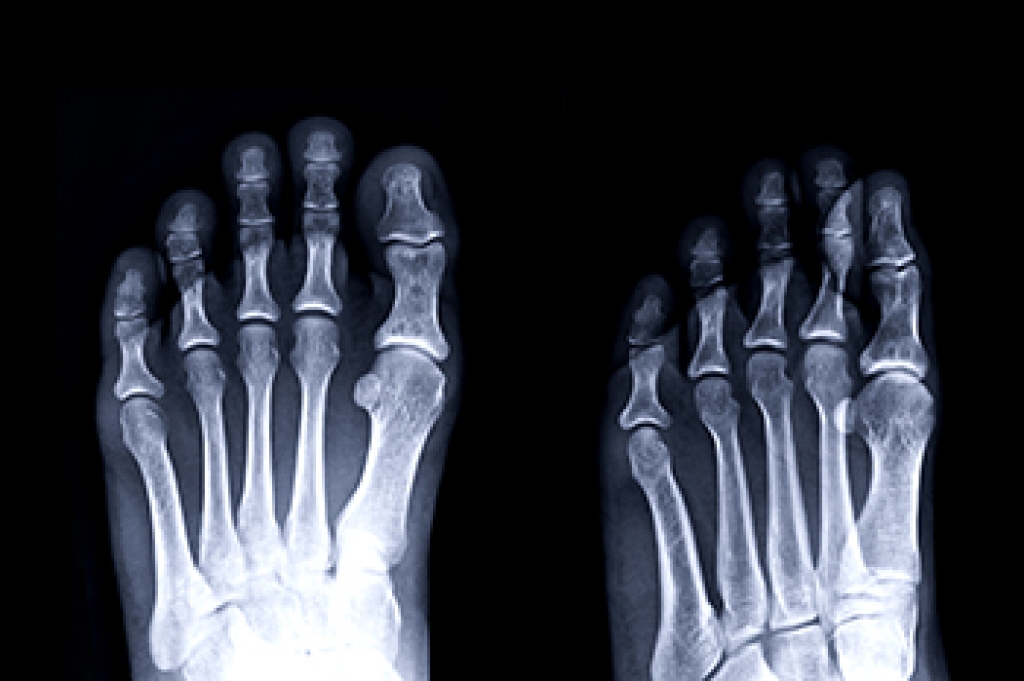

Heel pain can interfere with walking, standing, and daily activities. One of the most common causes of heel pain is strain on the thick band of tissue under the heel, termed the plantar fascia. Among other causes are inflammation near the heel bone, nerve irritation, or structur

al issues that affect how the foot absorbs pressure. A podiatrist performs a detailed exam, reviews activity history, and may use imaging to identify the source of heel pain. Treatment options include custom orthotics to reduce strain, guided stretching programs, activity modification, and medical procedures for persistent symptoms. Addressing alignment or gait problems can reduce repeated stress on the heel and surrounding tissues. Surgery may be discussed when other options do not provide lasting relief. If you experience heel pain that will not go away, it is suggested that you make an appointment with a podiatrist for an exam and treatment.